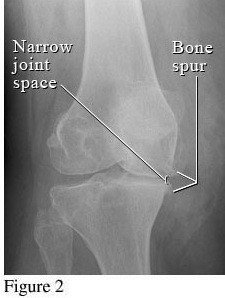

Hình ảnh so sánh giữa khớp bình thường và khớp bị thoái hóa khớp gối

Để phân biệt các giai đoạn của bệnh thoái hóa khớp gối, cần dựa vào phim X- quang theo tiêu chuẩn chẩn đoán thoái hoá khớp của Kellgren và Lawrence như sau:

Hình ảnh khớp gối trên phim X-quang: Khe khớp gần như bình thường, có thể có gai xương nhỏ.

Hình ảnh của khớp gối trên phim X-quang: Khe khớp hẹp nhẹ, có gai xương nhỏ.

Hình ảnh của khớp gối trên phim X-quang: Khe khớp hẹp rõ, nhiều gai xương kích thước vừa, đặc xương dưới sụn, đầu xương có thể bị biến dạng.

Hình ảnh của khớp gối trên phim X-quang: Khe khớp hẹp nhiều, gai xương có kích thước lớn, đặc xương dưới sụn, đầu xương biến dạng rõ.